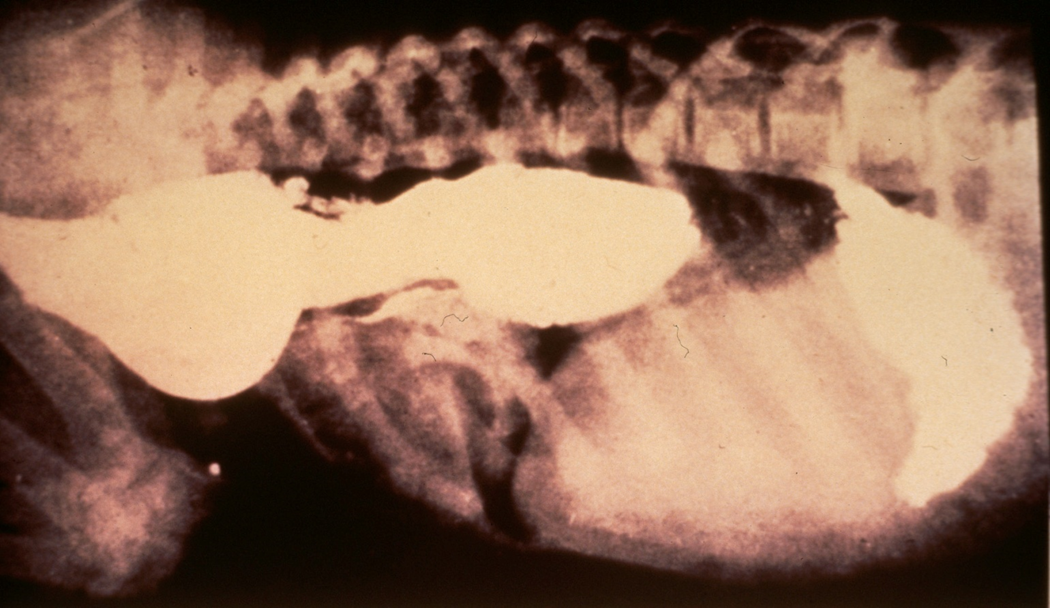

What virus of cats can cause this presentation

FIP, effusive or wet worm. The effusive or wet form – there is acute vasculitis with pleural and/or peritoneal effusions. The abdomen becomes progressively distended but is nonpainful on palpation. The volume of fluid is reflective of the chronicity of the infection.

Wet form is more common. Protein in fluid is very high (>35g/L); fluid cytology shows abundance of neutrophils and macrophages